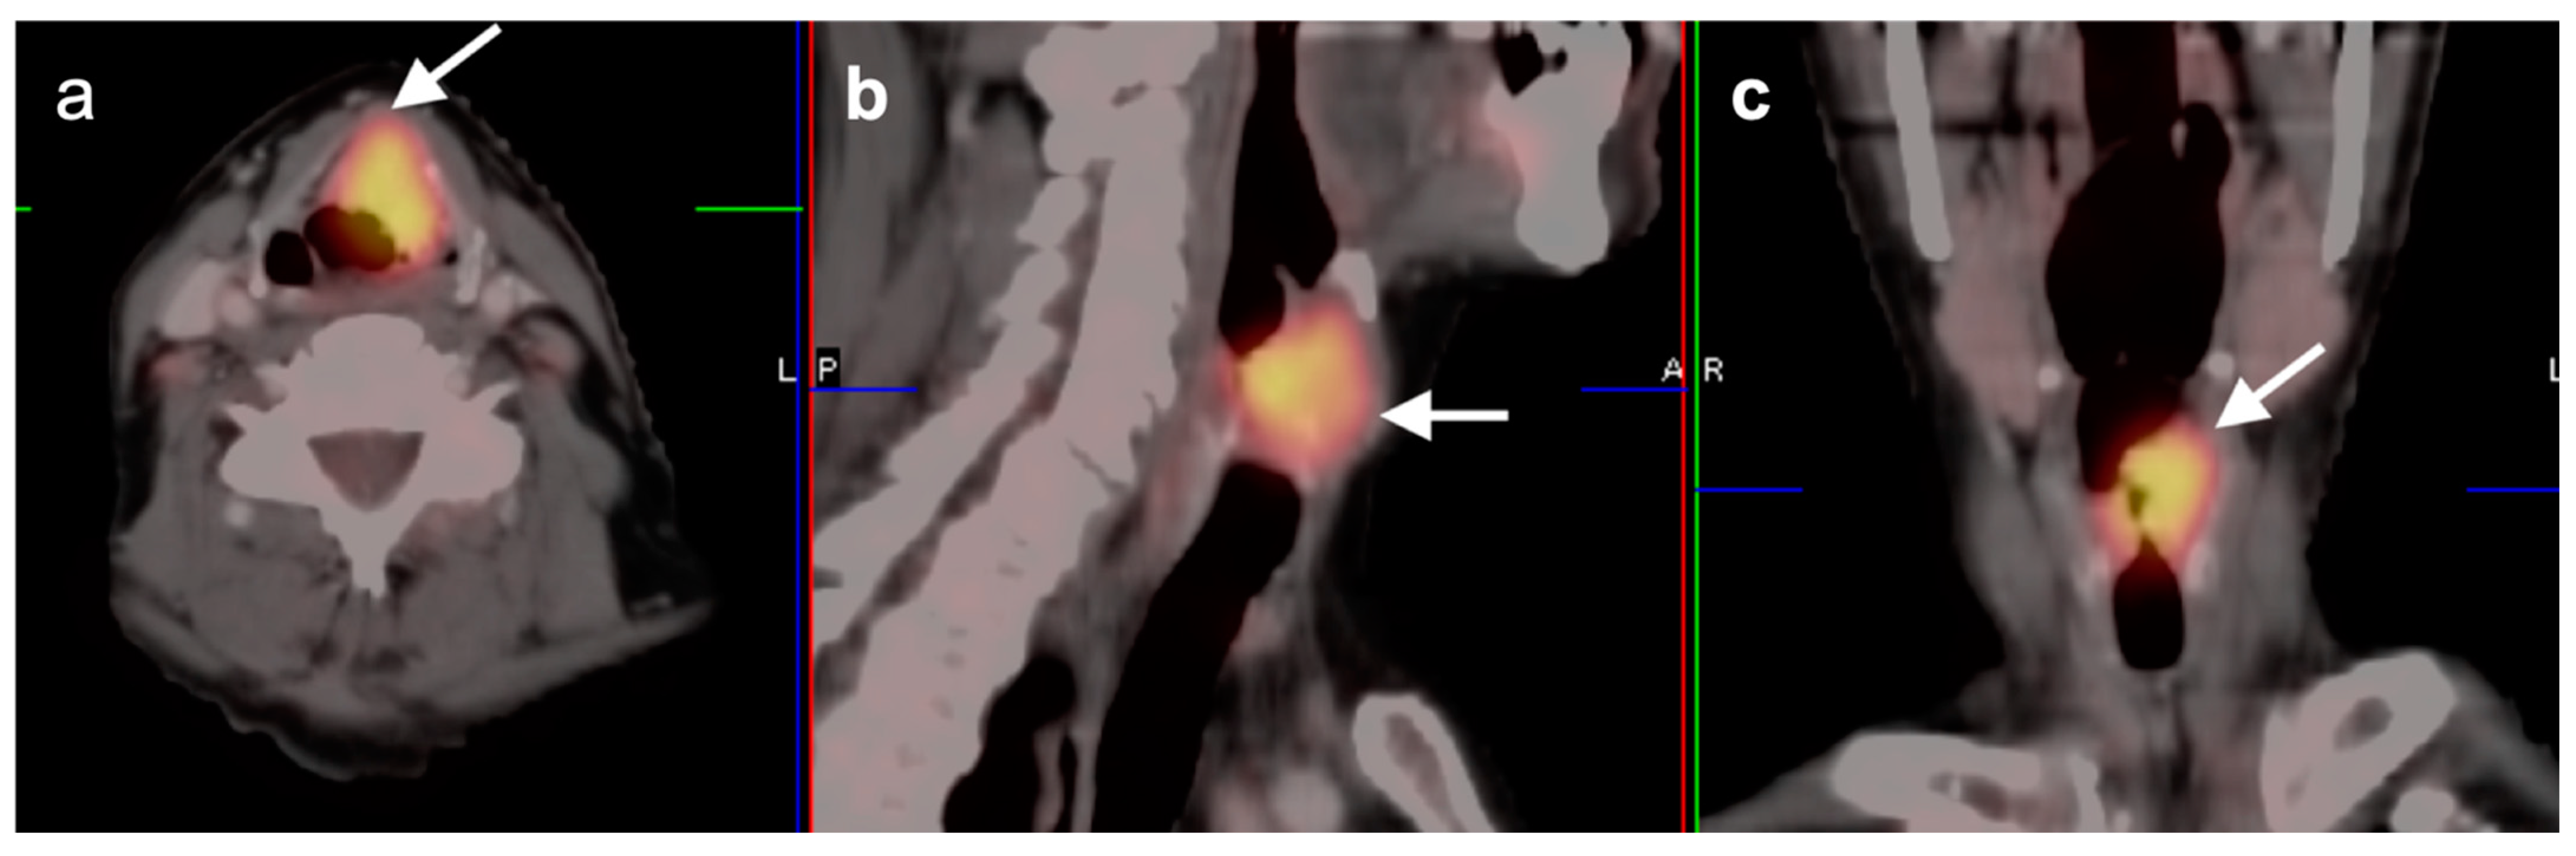

2.2. Squamous Cell Carcinoma of the Head and Neck (SCCHN)

2.3. Nasopharyngeal Carcinoma